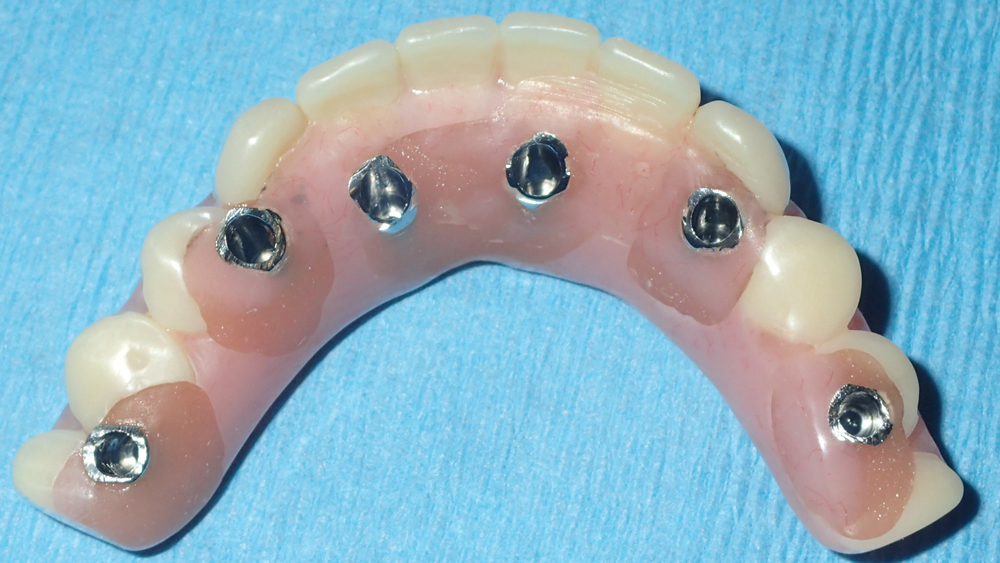

This patient was unhappy with the esthetics of her existing upper denture as well as the discomfort and instability caused by her loose-fitting mandibular partial denture. Although her concerns with the maxillary denture could be addressed with a new, more esthetic appliance, she preferred implant treatment for her mandible, where a fixed solution was needed to adequately restore function, stability and comfort.

Treatment plan:

The patient’s remaining mandibular teeth were extracted followed by immediate implant placement and delivery of a fixed provisional appliance. After integration of the implants, the prosthetic designs for the new upper denture and lower implant restoration were determined in tandem. Ultimately, the dual-arch restorations addressed the functional and esthetic challenges of the case while staying within the financial means of the patient, demonstrating the benefits of a flexible, multifaceted approach to restorative dentistry.